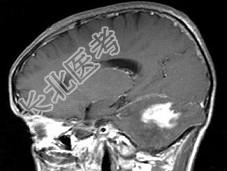

- 单项选择题男,41岁, 左枕部疼痛,右侧肢体乏力, 并渐进性加重半个月,右侧肢体乏力, 行走不稳,根据所提供图像, 最可能的诊断是 ( )

A、(小脑)血管母细胞瘤

B、(小脑)髓母细胞瘤

C、(小脑)炎性肉芽肿

D、(小脑)转移瘤

E、(小脑)星形胶质细胞瘤Ⅰ~Ⅱ级